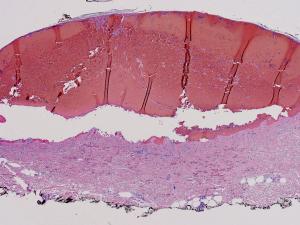

This is a very distinct, rare, and remarkable hemorrhagic rash, first recognized in 2006, with 7 known cases reported in the literature.